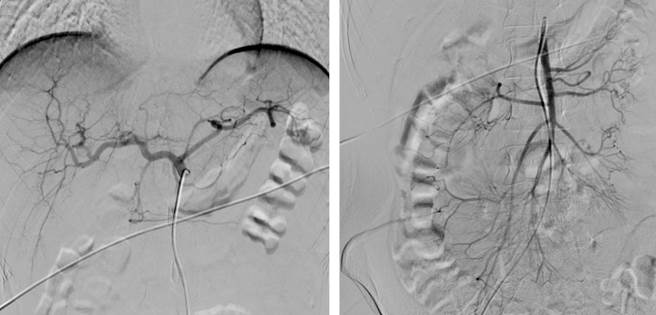

In preparation for a small intestine bleeding study, capsule endoscopy was planned. However, during her stay, she developed hemodynamic instability with tachycardia and hypotension, requiring stabilization and subsequent referral for angiography and embolization to control the bleeding. Upon arrival at the institution, she was hemodynamically stable and did not require vasopressor support. A second esophagogastroduodenoscopy was conducted, showing chronic erythematous gastritis and antral follicular gastritis. During follow-up, the patient once again exhibited signs of hemorrhagic shock, with ongoing profuse melena and significant anemia within less than 24 hours, with hemoglobin levels dropping from 9.7 g/dL to 3.9 g/dL. Consequently, an abdominal aortogram with selective mesenteric vessel study was performed, which was reported as normal for her age (Figure 1).

In this case, due to the patient’s hemodynamic instability, which necessitated transfusion support and vasopressor use, an abdominal angiography was initially performed but yielded negative results. Consequently, intraoperative enteroscopy was ordered as a last resort to determine the bleeding source and achieve prompt control, in line with current recommendations for managing small intestine bleeding1,6,7. Subsequently, the standard treatment of surgical resection with side-to-side anastomosis was carried out, resulting in a satisfactory postoperative course.